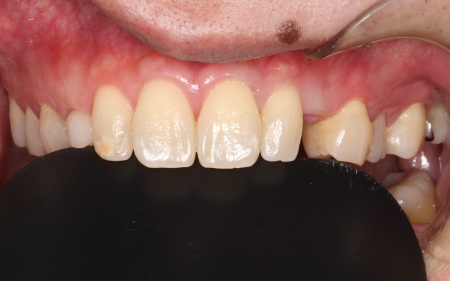

被せ物の素材は患者様と相談のうえ、自然な白さがあり変色や劣化が起こりにくいセラミックを選択しました。

まず手前の歯を削って土台を作り、精密な型取りを行います。

後日、完成したブリッジを装着し、噛み合わせなどに問題がないかを確認して治療を終了しました。

画像をクリックすると拡大・詳細コメントを確認いただけます